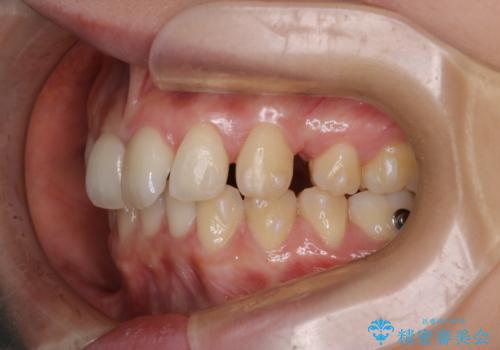

- 患者様は、上下の噛み合わせのバランスが悪く、特に上顎の前歯の突出を気にされて来院されました。診査の結果、下顎の歯並びに合わせて上顎を後方へ移動させる必要があると判断し、上顎の小臼歯2本を抜歯することを提案しました。目立たない矯正を希望されたため、**インビザライン(マウスピース矯正)**を選択。計画的にスペースを作りながら、バランスの取れた歯並びを目指しました。

治療はまず、上顎の小臼歯を2本抜歯し、そのスペースを利用して前歯を後方へ移動させました。インビザラインはアタッチメントを併用し、より効率的に歯を動かせるよう調整。定期的なチェックとアライナーの交換を続け、約3年かけて理想的な歯並びと噛み合わせを実現しました。治療後はリテーナーを使用し、安定した状態を維持。患者様からは「口元がスッキリし、横顔の印象も変わった」と嬉しいお声をいただきました。